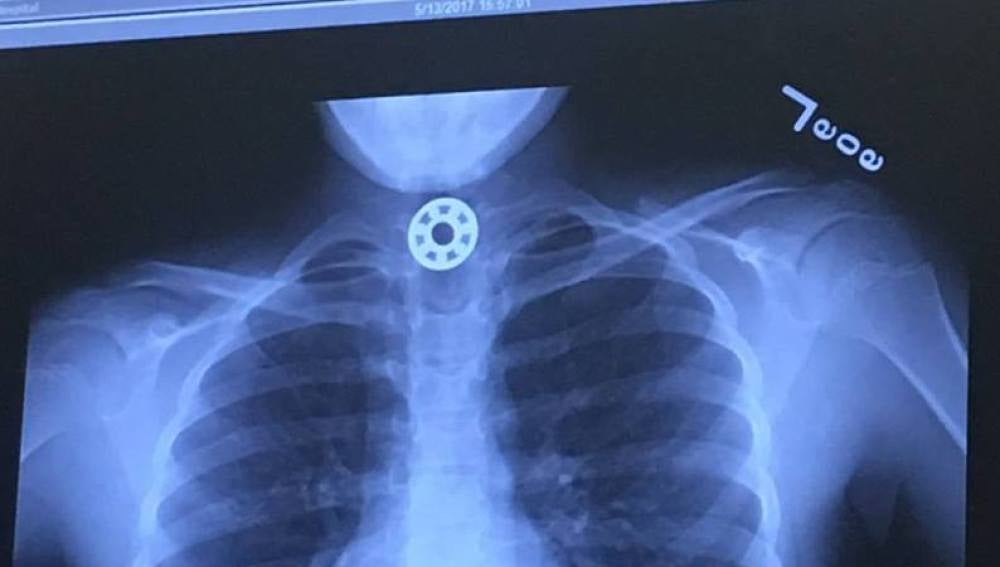

Radiografía de la niña que muestra el Fidget SpinnerFacebook

La madre, angustiada, trató de recibir ayuda médica rápidamente, pero los doctores no eran capaces de identificar dónde estaba el extraño objeto que la niña se había tragado. La pequeña fue trasladada al Hospital Infantil de Texas para que le realizaran una radiografía que mostró el juguete alojado en su esófago.